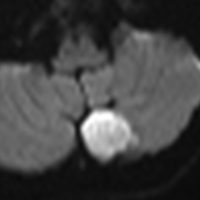

- MRI診断の最大の特徴は拡散強調画像 DWIで高信号になることです

小脳類皮のう胞

偶然発見された女の子のものです。左のCTで石灰化があります。右の拡散強調画像 DWI で白く高信号に描出されるのが特徴です。手術では腫瘍内部に毛髪がたくさんありました。後下小脳動脈に強く癒着していて,脳軟膜からの剥離もできませんでしたが,完全摘出しました。無症状でも”完全”摘出 complete removal するべきです。